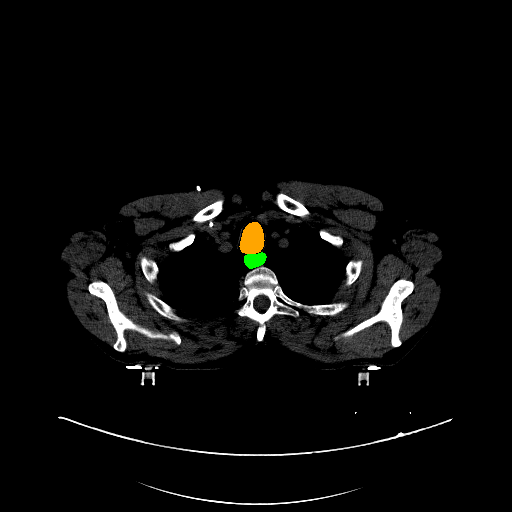

Case Study 3: Multi-Organ Segmentation

The cognition of artificial intelligence is important for computer-aided diagnostic. Multi-organ segmentation can help the machine understand the structure of the human body, which is very important for all the relevant tasks. Therefore, some research has focused on single- or multi-organ segmentation tasks, such as the liver([79, 80]) and the pancreas([81, 82]). In this case study, we use a VNet-based neural network to solve the multi-organ segmentation challenge, SegTHOR, [83]. The SegTHOR challenge includes about 40 CT images of the chest, and aims at the segmentation tasks of the heart, aorta, trachea, esophagus, and further more.

VI-1 Workflow and Implementation

As Fig. 11 shows, The workflow of this case study includes six parts: “input”, “pre-processing”, “dataset management”, “neural network”, “visualization”, and “analysis”. The “input” includes images of the chest and annotations.

“Pre-processing” rescales the range of the image values with a window width and a window level. Then, the input images are re-sampled with the “resample” tool to change their size. The “dataset management” function subsequently splits the dataset into a training and a testing set randomly, yet reproducibly.

“Neural network” employs VNet to train and validate the model, which can be used to segment organs from the chest. Then, the segmented images can be visualized via the “organ visualization” option, and the results can be analyzed with the “result analysis” tool to generate an MS-Excel based report.

VI-3 Result and Visualization